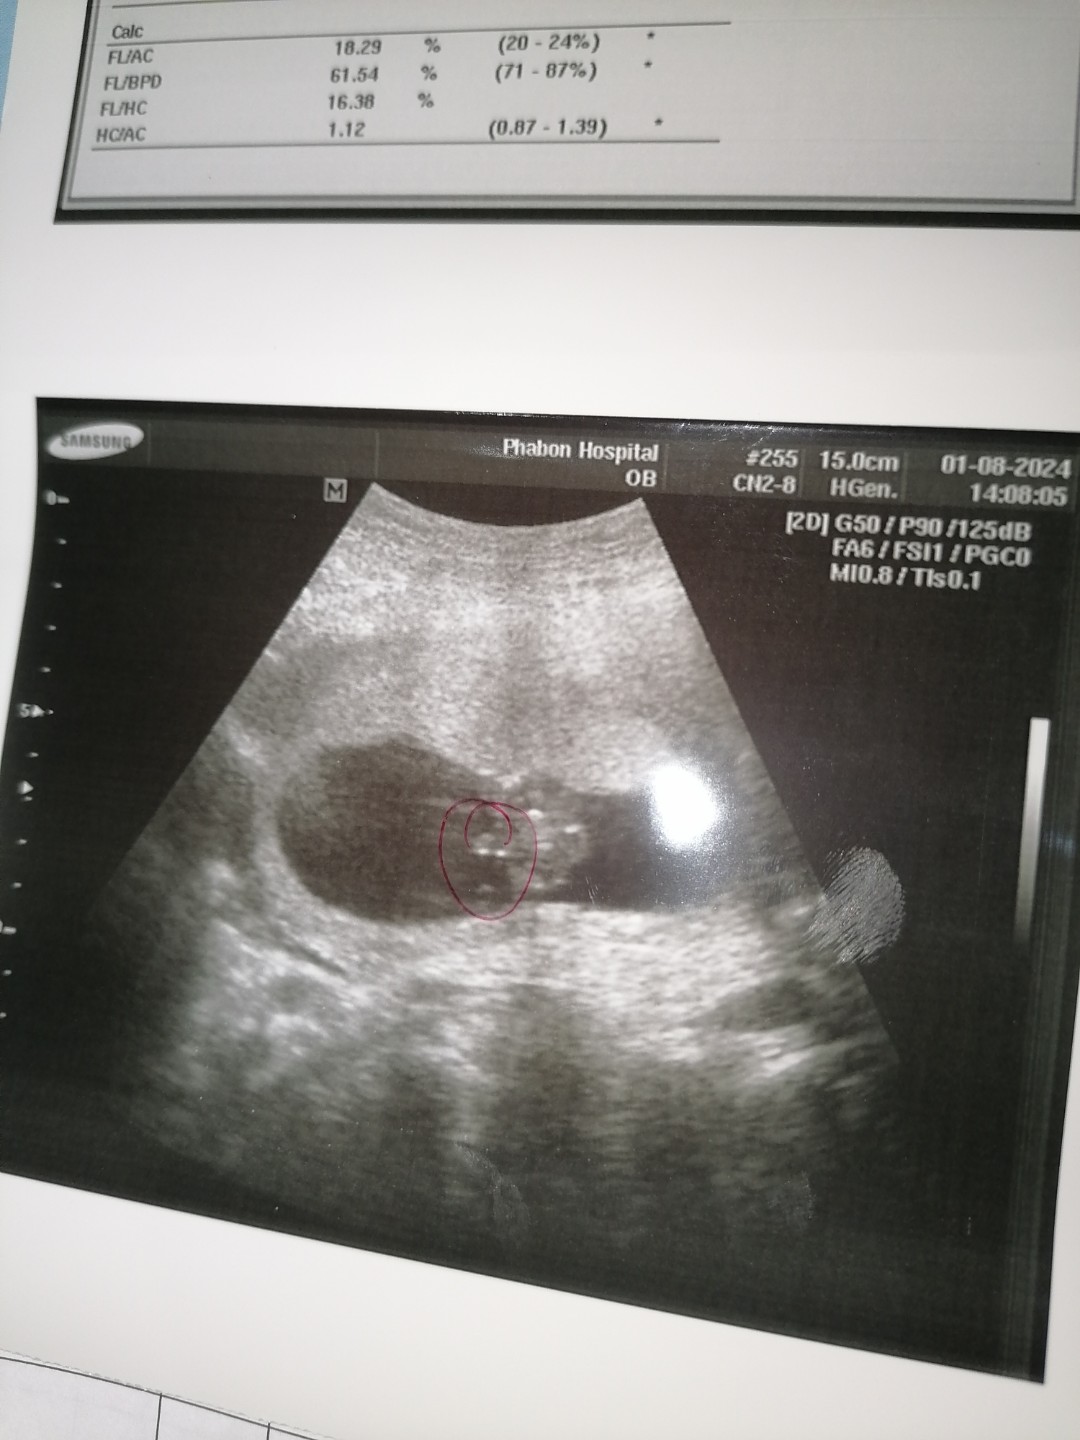

อัลตร้าซาว 18 weeks พอจะทราบเพศน้อง ยังคะ หมอแจ้งว่า อาจจะเป็น ผู้ชายค่ะ

ของเราซาวรู้เพศจั้งแต่ 16 วีคคะ น้องอ้าขาพอดี จู๋โผล่คะ หมอจะคอนเฟิมชัวร์ๆ อยุที่ท่าน้องด้วยคะ ว่าอยุท่าไหนเห้นชัดไหม ส่วนใหญ่ซาวดูเพศจะแม่นยำตอน 20 วีคขึ้นไปคะ อวัยวะเพศภายนอกสมบูนแล้วแต่ทั้งนี้ทั้งนั้นอยุที่ท่าของน้องด้วยคะ ว่าจะเอื้อต่อการมองเห้นไหม